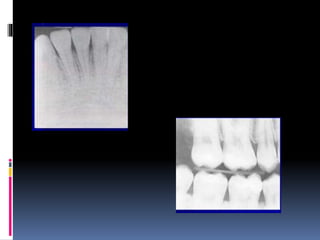

Lighter radiographs (underexposed/

underdeveloped radiographs).

Darker films (overexposed /overdeveloped /high

density)